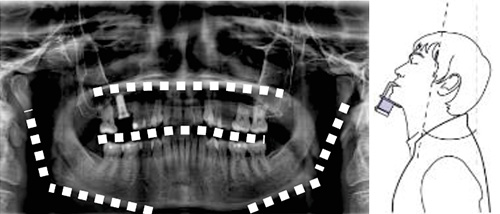

●フランクフルト平面のずれ

咬合平面が「へ字」にカーブ

→顎の上げすぎ、チンレストが高すぎる